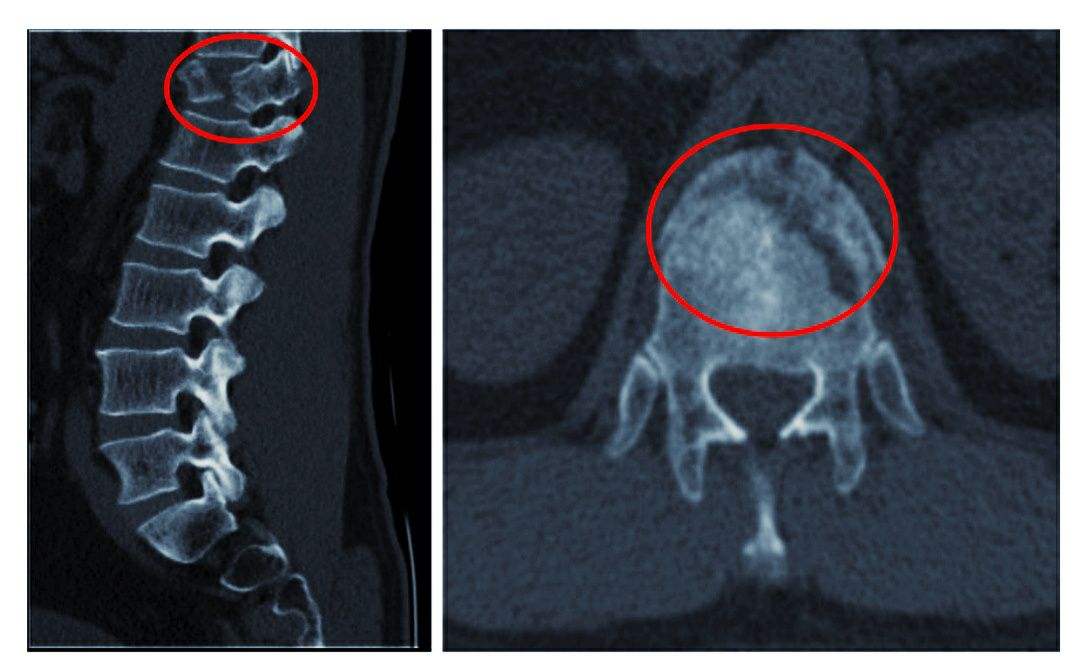

2、椎體緣、關(guān)節(jié)突、鉤椎關(guān)節(jié)骨贅形成

骨贅即骨質(zhì)增生俗稱為骨刺,是指骨關(guān)節(jié)邊緣上由于長期慢性損傷引起瘢痕組織增生,天長日久可產(chǎn)生鈣質(zhì)沉著變成骨質(zhì)而形成的。

由于椎間盤的退變,其后果必然導(dǎo)致頸椎生理曲線的改變,破壞了椎體間的平衡。久之,機(jī)體為了抵抗疼痛,使神經(jīng)免受刺激,建立新的平衡,而產(chǎn)生代償性骨贅,來穩(wěn)定脊柱。當(dāng)然骨贅形成的主要原因是急慢性損傷,骨贅的形態(tài)及部位與損傷的性質(zhì)等有關(guān),骨贅的大小與年齡有關(guān),與癥狀的輕重不一定成正比。若骨贅發(fā)生于椎間孔或椎管附近,可產(chǎn)生神經(jīng)根、椎動脈或脊髓受壓癥狀。